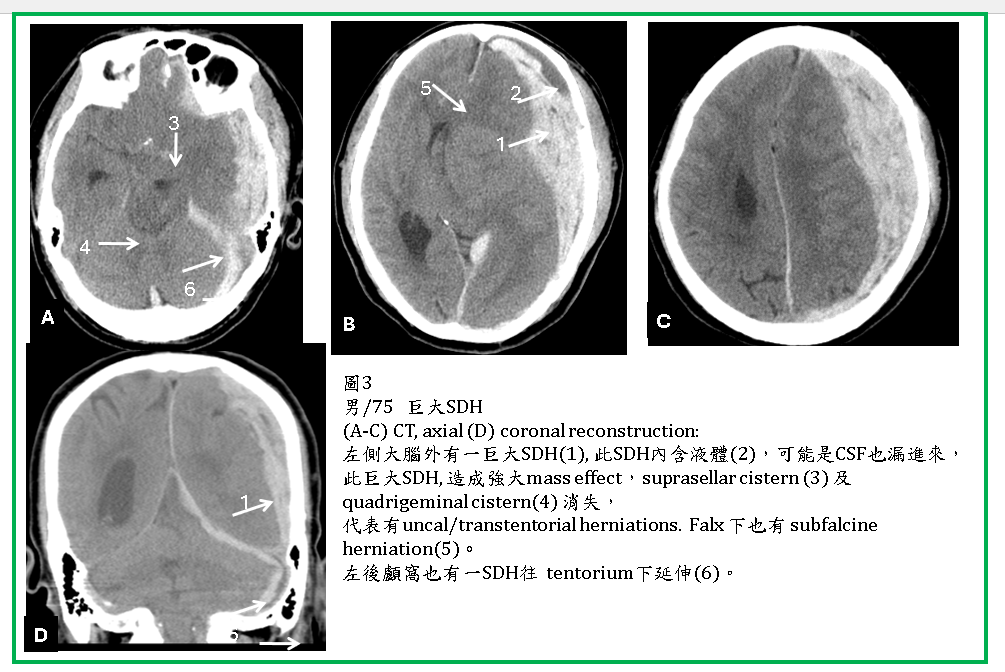

典型的ASDH呈現鐮刀形或新月形的高濃度區域(圖1,2) ,因它會往前後滲透,所以厚度不會太厚,可是腫塊效應也是很強,嚴重時也會造成uncal及transtentorial herniations (圖2,3) 。

ASDH有時往後會延伸到小腦天幕下的硬腦膜下腔(圖1-3)。在CT橫切面,小腦天幕下SDH呈現片狀,極易被誤為是腦內血塊(ICH) (圖3,4)。SDH有時會在大腦半球間裂(interhemispheric fissure) (圖5),或由大腦額頂葉外的SDH滲透進入interhemispheric fissure 。

有些ASDH會混合較低濃度的液體,可能是血塊尚未凝固(圖3- ,或可能是因為蜘蛛網膜也有裂傷,因此CSF也流入硬腦膜下腔,CSF與血塊相混合(圖3)。